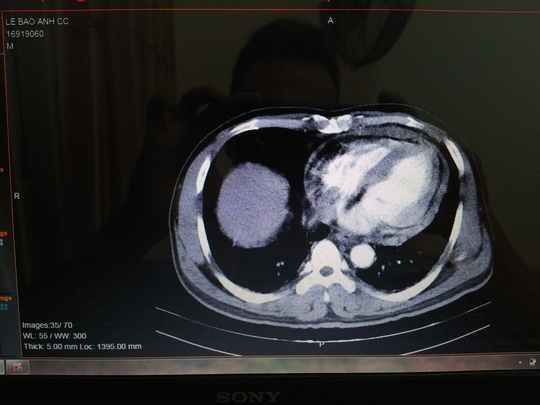

Qua siêu âm, chụp CT các bác sĩ phát hiện bệnh nhân bị tổn thương rách tụ dịch cơ tim (tâm thất phải vùng mỏm), tràn dịch màng tim. Trước tình trạng nguy kịch, bệnh viện đã tiến hành hội chẩn toàn viện, quyết định mở ngực khẩn cấp, vá lỗ thủng tim, cầm máu cứu bệnh nhân, dù thời điểm này chưa thân nhân bệnh nhân tại bệnh viện.

Vết thương thấu tim của người lái xe ôm. Ảnh NLD |

Bác sĩ Nguyễn Kim Anh, Trưởng khoa Lồng ngực - Mạch máu của bệnh viện cho biết trong quá trình mổ khảo sát, gặp sự cố tràn máu màng tim, các bác sĩ hút ra được đến 0,5 lít máu. Sau đó ,máu vẫn tiếp tục chảy ra ở vết thương theo nhịp bóp của tim, tương đồng với kết quả siêu âm nhận định trước mổ. Các bác sĩ đã khâu vết thương và cầm máu thành công - theo Dân Việt.